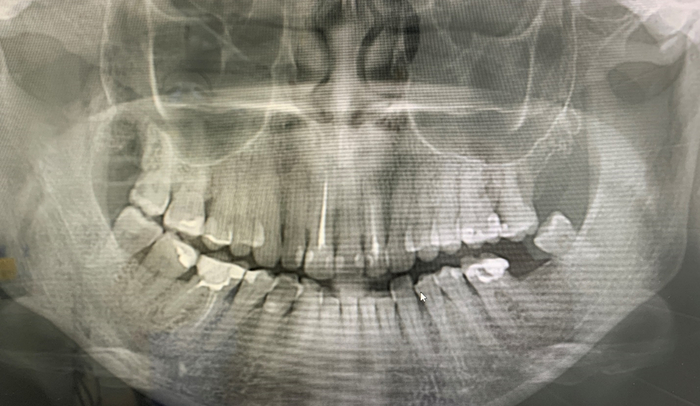

После чего делаем контрольный снимок и зашиваем наглухо дырку в пазуху.

На снимке чисто

Это у меня улетел имплант в Гайморову пазуху. Слюноотсосом достать было не вариант, так как пришлось бы раскурочить челюсть, которую и так нужно было наращивать, отчего впредь импланты туда поставить было бы крайне трудно. Пришлось отправить в стационар, где аккуратно это все дело извлекли под наркозом. Класть пациента лучше к тем, кого знаешь и в ком уверен, дабы не усугубили ситуацию.